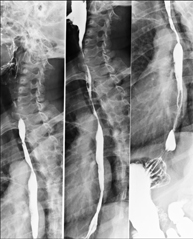

Tècnica que usa els raigs X a través de la qual s'obtenen imatges de la columna dorsal per al seu estudi. Indicacions: traumatisme, dolor, escoliosi. - Esofagograma

Prova diagnòstica que consisteix en obtenir imatges radiològiques en moviment de l'esòfag mitjançant l'ús de raigs X (fluorosòpia) i d'un contrast opac baritat que s'administra per via oral.

Tècnica que usa els raigs X a través de la qual s'obtenen imatges de l'abdomen (estómac, intestí prim, intestí gros, fetge, ronyons, bufeta, pelvis òssia, etc.) per al seu estudi. - RX Columna lumbar

Tècnica que usa els raigs X a través de la qual s'obtenen imatges de la columna lumbar per al seu estudi. - TEGD (trànsit esòfag-gastro-duodenal)

Prova diagnòstica que consisteix en obtenir imatges radiològiques en moviment de l'esòfag, estómac i duodè mitjançant l'ús de raigs X (fluoroscòpia) i d'un contrast opac baritat que s'administra per via oral. - Trànsit intestinal

Prova diagnòstica que consisteix en obtenir imatges radiològiques en moviment de l'esòfag, estómac, duodè i intestí prim mitjançant l'ús de raigs X (fluoroscòpia) i d'un contrast opac baritat que s'administra per via oral. - Ènema opac doble contrast

Tècnica que usa els raigs X a través de la qual s'obtenen imatges de tota la columna vertebral per al seu estudi, amb la valoració especialment de la presència d'escoliosi i dismetries pèlviques.

Tècnica que usa els raigs X a través de la qual s'obtenen imatges de tota la columna vertebral per al seu estudi, amb la valoració especialment de la presència d'escoliosi i dismetries pèlviques. - Telematria EEII (Extremitats Inferiors)